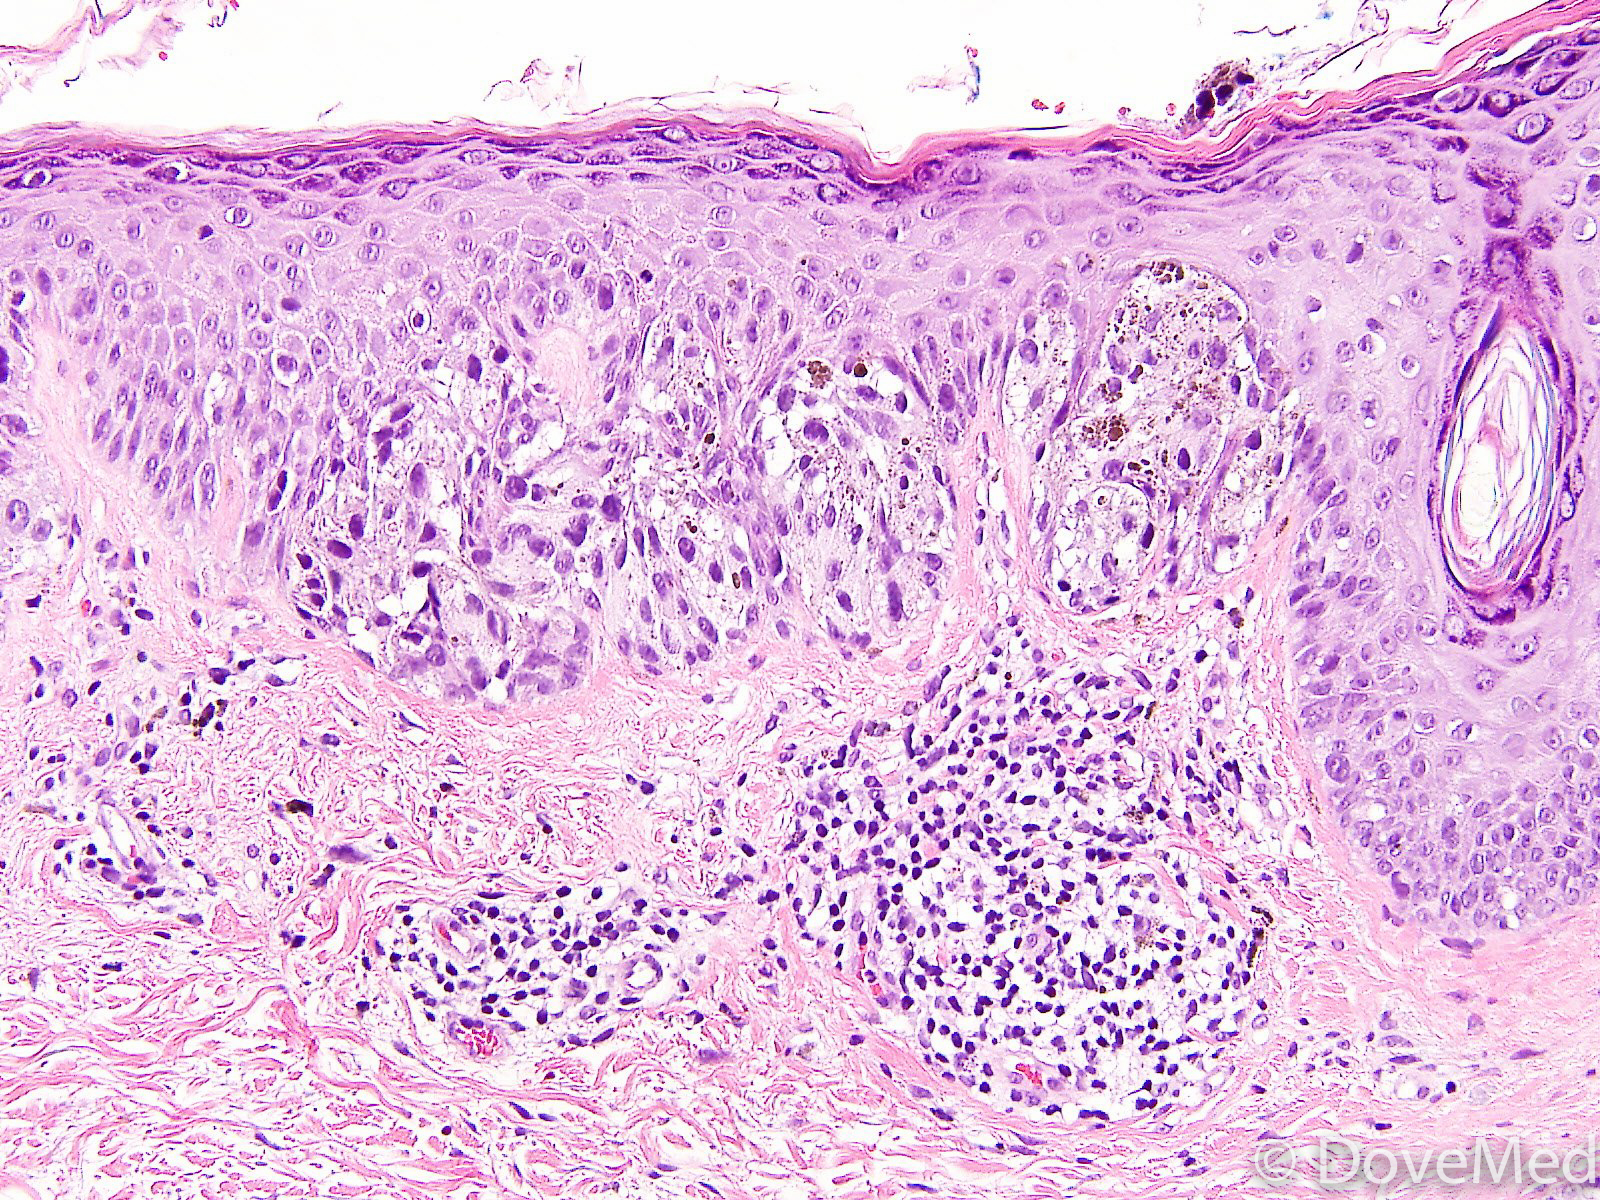

From www.dovemed.com

Melanoma In Situ of Skin Melanoma Under Skin Melanoma is a skin cancer that can show up on the skin in many ways. When it's diagnosed early, most people. Learn the signs and symptoms of melanoma skin cancer. Unusual moles, sores, lumps, blemishes, markings, or changes in the way an area of the skin looks or feels may be a sign of melanoma or another type. Melanoma is. Melanoma Under Skin.